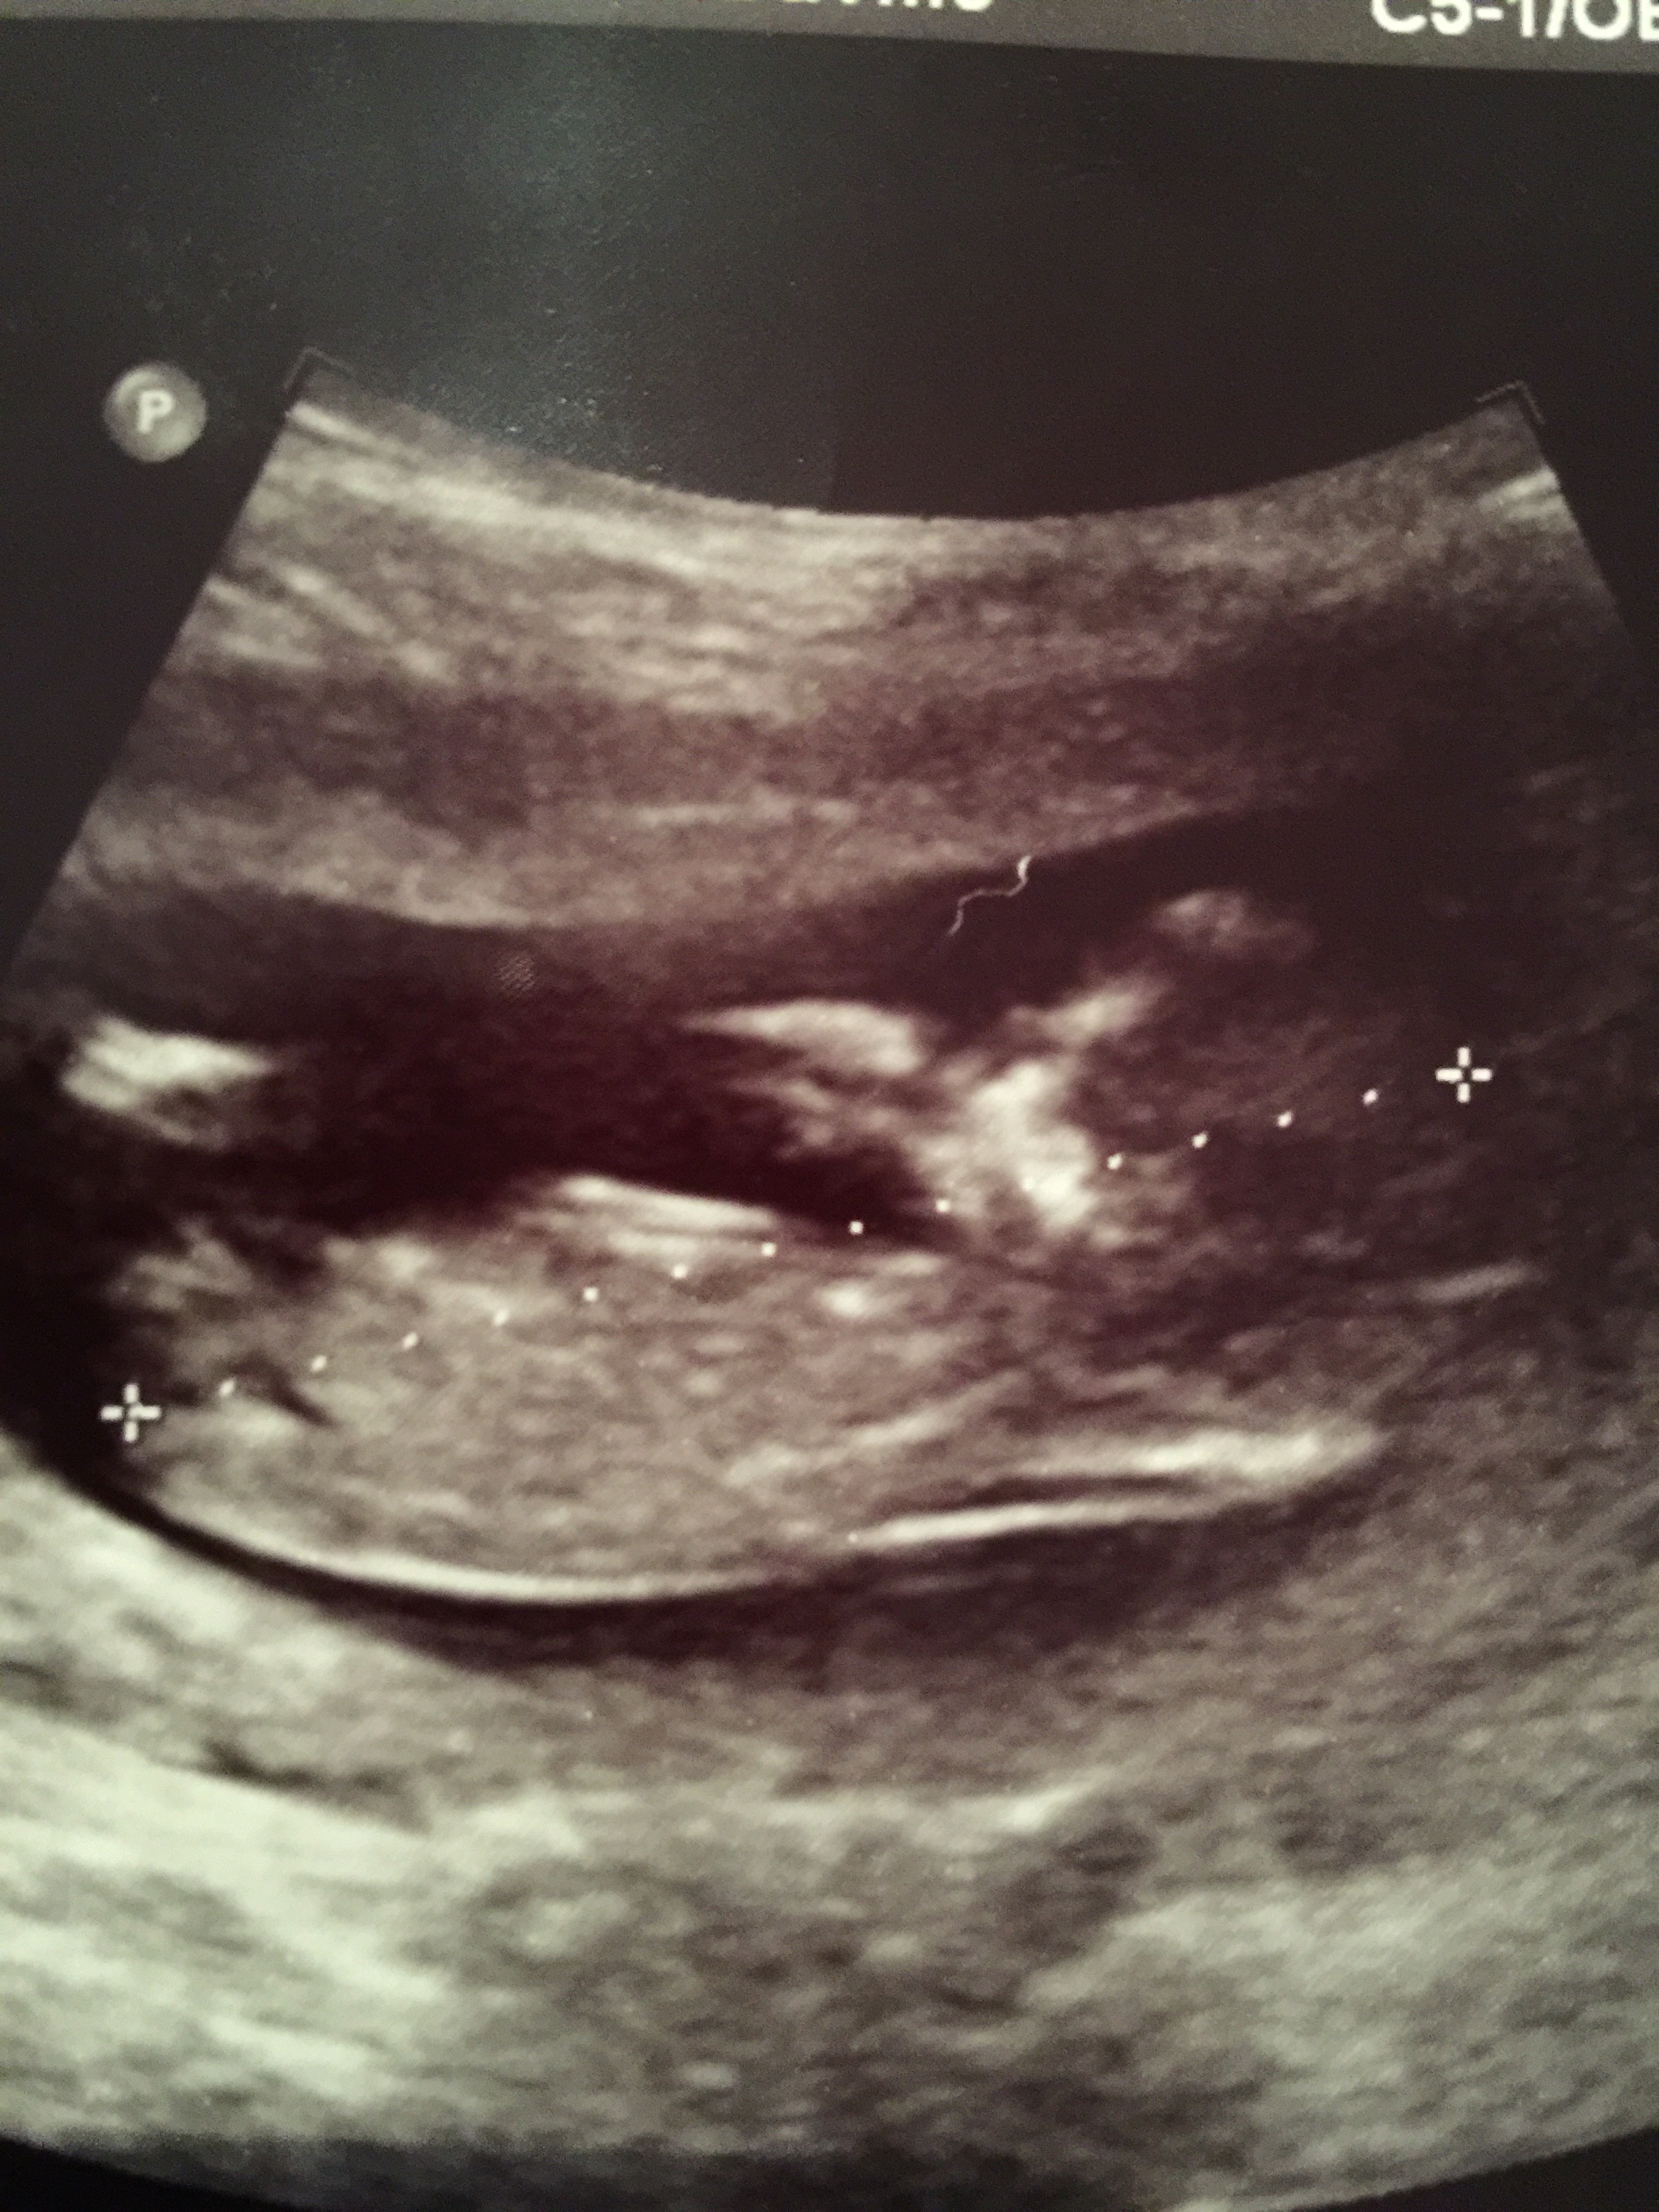

Hubby didn't want to find out but curiosity has the better of me, would love to know your guesses![]()

18w5d girl or boy?

maybe girl. Any 12-14 week nub pics?

Can anyone see the 3 little white lines? Or are you guessing on absence of boy parts? Xxx

Can anyone see the 3 small white lines or is it just my untrained eye?

girl